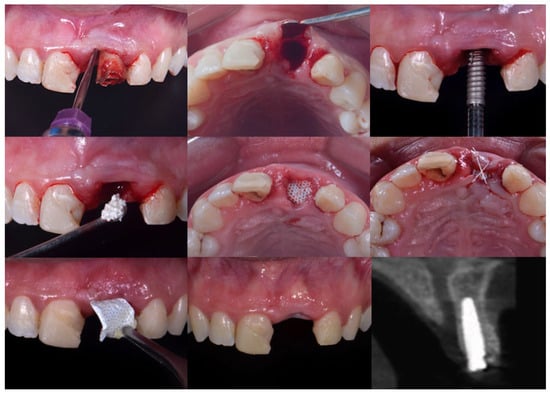

Figure 4.

Clinical sequence of the surgical and clinical steps: the tooth extraction; an inspection of the alveoli; immediate implant placement; xenograft material placed on the surgical site; d-PTFE intentionally exposed; suture with Teflon; membrane removal after 21 days; and final clinical and radiographic aspect of the area.